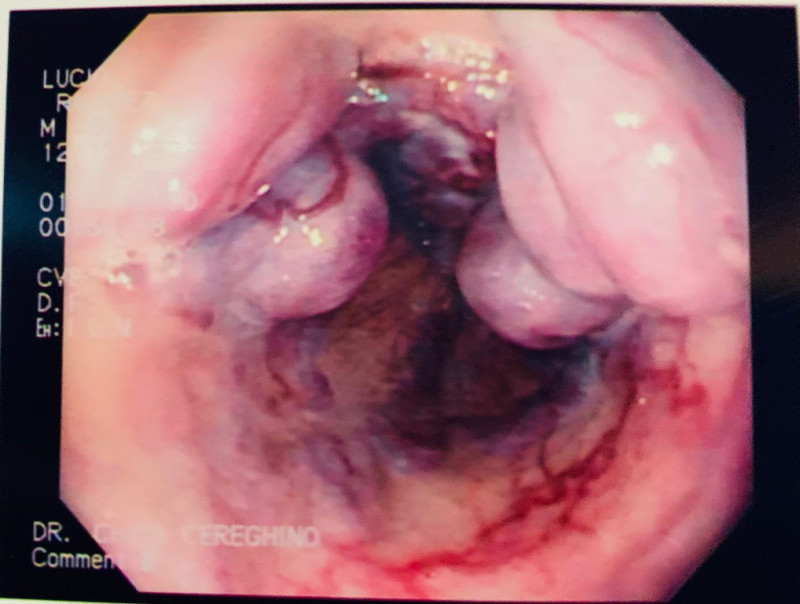

Cálculo gigante por coledocoliatisis